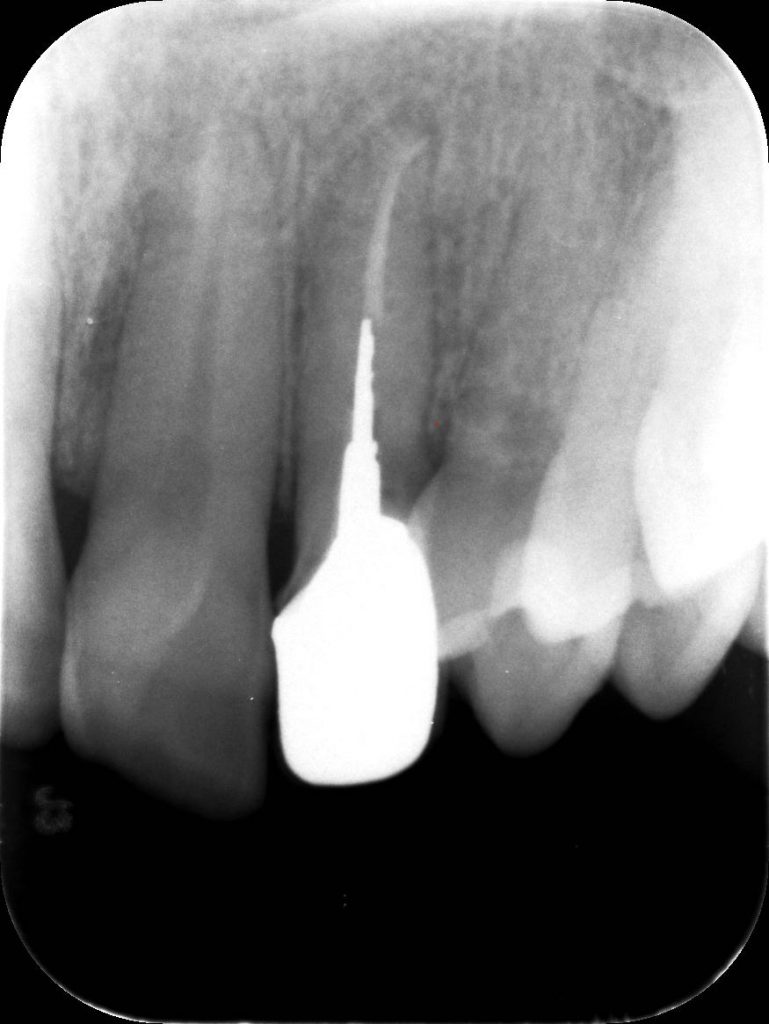

La pz N.G. di anni 52 (ASA 1) viene visitata nel mese di settembre 2017 per la mobilità ed inestetismo dell’elemento protesico 22, (foto iniziali sequenza 1) si evidenzia una frattura parziale della radice, si decide per l’estrazione ( foto sequenza 2) e sostituzione dell’elemento con un restauro implanto-protesico. Purtroppo la scarsa quota ossea apicale all’alveolo post-estrattivo (foto 2 rx) e l’alta valenza estetica dell’elemento ci rende cauti e si programma una socket preservation post estrattiva con l’ausilio delle membrane di prf (foto prf e socket sequenza 3 e 4). Durente i 5 mesi di guarigione la pz porta una protesi parziale mobile (foto 5,2) , a guarigione del sito post estrattivo si evidenzia una buona conservazione dei volumi osseo-gengivali,(foto guarigione sequenza 6) se pur presente una recessione distale all’elemnto 21.Nel mese di febbraio 2018 si procede all’inserimento di un impianto max-stability 3,75x12mm disegnando un lembo anticipato palatino per consentire un aumento dei tessuti vestibolari suturando con tecnica rool flap e trasformando l’elemento parziale mobile in una corona singola a carico immediato sul moncone temporameo applicando i concetti protesici bopt , (foto impianto moncone protesi provvisoria sequenza foto 7-8-9). Durante il periodo di maturazione dei tessuti molli vengono apportate opportune modifiche ai profili del provvisorio al fine di dare maggior spazio al tessuto gengivale, ( fotosequenza 10).Dopo circa 2 mesi dal protesizzazione provvisoria si è proceduto alla realizzazione del manufatto protesico con tecnica chair side sirona con l’ausilio del t-base (foto sequenza 11-12-13), realizzando in una sola seduta una corona in disilicato, ottenendo un risultato più che soddisfacente (Foto 14). Nel controllo a 3 mesi dal carico definitivo si apprezza la perfetta conservazione dei livelli ossei e gengivali. (foto sequenza 15).concludo con un follow up a 18 . Tengo a sottolineare che un caso come questo è stato conducibile con buoni risultati solo grazie alla piena fiducia della pz e alla sua massima motivazione e collaborazione. Ad oggi la pz sorride soddisfatta del risultato. E questo rappresenta la massima ricompensa di chi dedica tutto se stesso alla professione.

rx follow up 18 month post loading